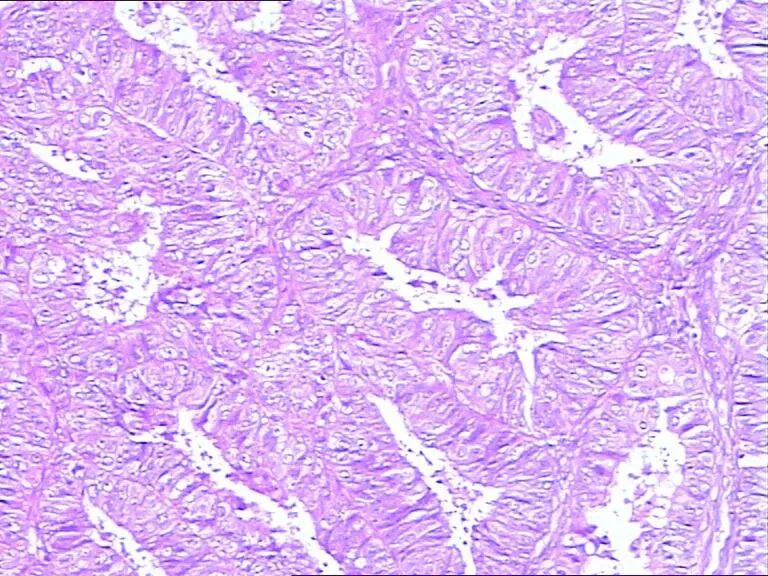

山东省德州市中医院 | 徐连泉 患者家属投诉我 我却成了他的“朋友” 由于种种原因,近年来,医患关系越发紧张。患者或其家属动辄就将医生投诉,病理医生也未能幸免。 而我,却因为患者家属的一次投诉,竟成了对方的“朋友”。 三年前,38岁的患者王某因不规则阴道流血3个月来我院妇科就诊。彩超显示其宫腔内膜增厚,遂刮宫送检。 切片出来后,我在显微镜下仔细观察分析,发现大部分腺体显著密集,大小不等,个别呈筛状,上皮细胞大多失去极性,轻-中度异型,可见核仁及核分裂像,间质稀少,部分消失。最后签发病理报告: (宫腔)高分化子宫内膜样腺癌 报告发出后,妇科医生便着手给王某准备手术,而王某的家属却非要先借片去省级医院会诊。 这当然无可厚非,我也同意。但在办理借片手续时,我按有关规定请借片人也就是王某的丈夫交纳100元的押金,等还切片时凭押金收条退回押金。 但是,他拒绝了!他认为片子本来就是用他媳妇身上的肉做出来的,凭啥不能给他,还非要交押金才能借片子? 我很无奈,说:这是国家及省里的有关文件规定的。并找出相关的文件给他看。然而,他根本不看,只说交押金还必须还片子就是不行,否则就投诉我。 果然,不一会儿,我就接到了医院医务科的电话,说有人把我投诉到了市长热线12345,让我去医务科给予答复。无奈,我只得赶紧带着国家卫生计生委及原山东省卫生厅(山东省卫生计生委)发布的相关文件去找医务科长。 国家卫生计生委和国家中医药管理局联合发布的《医疗机构病历管理规定(2013年版)》以及原山东省卫生厅发布的《山东省临床病理诊断与技术操作规程(试行)》中规定: 既然是“借,”就必须有“还”。如何保证病人及时归还切片?通常就是让借片者交纳一定数额的押金,并留下借片者的身份信息及联系电话。借片者非患者本人时,其须同时出示患者的身份信息,并一起留下。 看到国家及省里的相关文件,医务科长也只能按相关文件办事,如实回复12345。12345让患者家属遵从相关文件的规定。 最终他交纳押金,借走切片。 第二天,省里的会诊报告出来了,是:(宫腔)子宫内膜非典型增生,建议一月后复查。 一月后,患者的阴道仍然流血,她就直接去了上次会诊的那家省级医院。在那里,她再刮宫送检,病理诊断为子宫内膜样腺癌。 患者当即就入院做了手术,术后病理检查发现,宫腔内的癌组织已侵及子宫肌层。 还切片时,患者的丈夫再无原先的满脸怒气,不仅为他早先的行为表示道歉,还非要请我吃饭,要和我交“朋友”。 在我的询问下,他将媳妇去省里会诊、在家等待、去省里复诊、再刮宫送检以及手术治疗的整个过程详细的讲与我听。说是早信我的诊断早手术就好了。 当然,作为一名医生。治病救人是我的职责,饭,自然是不会去吃的。 此后,他还真就把我当成了“朋友”,每当他及他的家人甚至他的亲戚、朋友身体出现了什么病症,首先想到的就是向我咨询。 需要门诊或住院治疗的,全都首先来我们医院。我也的确感到了“麻烦”,但这样的“麻烦”却也让我内心感到一丝的欣慰: 还有什么能比患者对自己的信任更高兴呢! 文字由徐连泉原创,部分图片来源于网络,版权归病理大师所有。